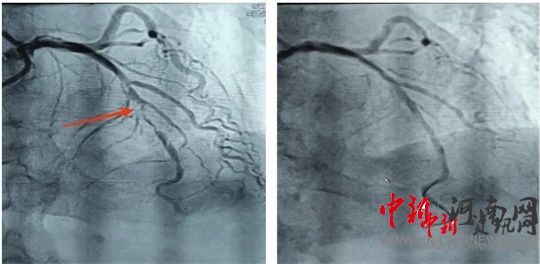

術(shù)前 術(shù)后

造影結(jié)果顯示,前降支中段次全閉塞。經(jīng)過(guò)充分預(yù)處理病變后,應(yīng)用一枚藥物球囊進(jìn)行治療。隨后,患者癥狀明顯緩解,生命體征恢復(fù)平穩(wěn),送入重癥監(jiān)護(hù)室進(jìn)行過(guò)渡觀察。